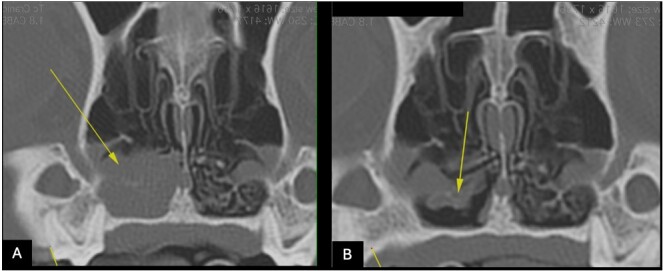

Epistaxis is defined as bleeding from the nasal cavity and can be related to systemic causes leading to coagulation disorders, most commonly hemoparasitosis, or to localized changes in the nasal cavity itself (e.g., intranasal neoplasms). Transmissible venereal tumors (TVT) are malignant round cell neoplasms characterized by an anomalous proliferation of tumor cells disseminated mainly by direct contact between animals. Although transmitted sexually, transmission through contact with mucous membranes and skin tissue can also occur, including the nasal cavity. Although rare, it can have significant clinical implications because it is difficult to diagnose. The diagnosis is made by physical examination, imaging tests (computed tomography and rhinoscopy), and histopathological analysis, which is the gold standard. Treatment is based on the use of chemotherapeutic agents, with vincristine as the drug of choice. This study reported a case of intranasal TVT in a 4-year-old French bulldog and addressed its clinical characteristics, diagnosis, and treatment. It also reported the importance of early recognition of the condition and changes in imaging tests to better understand and manage this atypical presentation.

Abstract Image